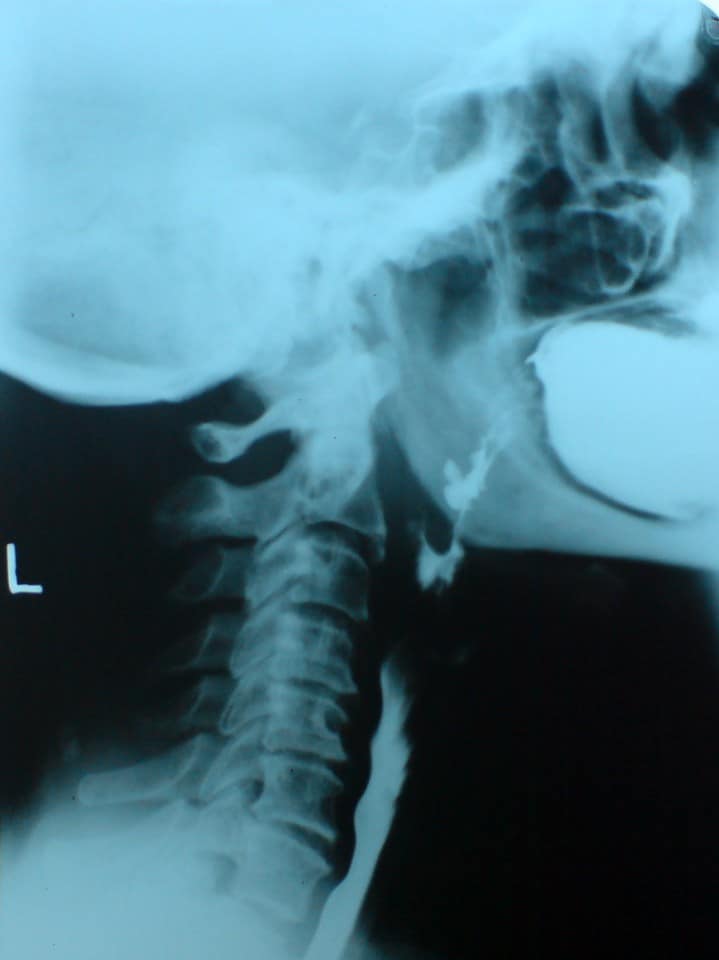

Swallowing is an important part of eating and drinking. If the process fails and the bolus to be swallowed mistakenly goes into the trachea, then choking or pulmonary aspiration can occur. In the human body, such incidents are prevented by an automatic trapdoor-like inversion of the epiglottis to temporarily cover the larynx and close off the upper airway, controlled by a complex reflex that facilitates the elevation of the hyoid bone and thyroid cartilage at the same time. The body will also initiate a cough reflex to expel any unwanted material that have accidentally entered the airway. A separate gag reflex, which involves the elevation of the uvula and tightening of the soft palate, prevents food from wrongly entering the nasal cavity above during swallowing.

The primary laryngopharyngeal protective mechanism to prevent aspiration during swallowing is via the closure of the true vocal folds. The adduction of the vocal cords is affected by the contraction of the lateral cricoarytenoids and the oblique and transverse arytenoids (all recurrent laryngeal nerve of vagus). Since the true vocal folds adduct during the swallow, a finite period of apnea (swallowing apnea) must necessarily take place with each swallow. When relating swallowing to respiration, it has been demonstrated that swallowing occurs most often during expiration, even at full expiration a fine air jet is expired probably to clear the upper larynx from food remnants or liquid. The clinical significance of this finding is that patients with a baseline of compromised lung function will, over a period of time, develop respiratory distress as a meal progresses. Subsequently, false vocal fold adduction, adduction of the aryepiglottic folds and retroversion of the epiglottis take place. The aryepiglotticus (recurrent laryngeal nerve of vagus) contracts, causing the arytenoids to appose each other (closes the laryngeal aditus by bringing the aryepiglottic folds together), and draws the epiglottis down to bring its lower half into contact with arytenoids, thus closing the aditus. Retroversion of the epiglottis, while not the primary mechanism of protecting the airway from laryngeal penetration and aspiration, acts to anatomically direct the food bolus laterally towards the piriform fossa. Additionally, the larynx is pulled up with the pharynx under the tongue by stylopharyngeus (IX), salpingopharyngeus (pharyngeal plexus—IX, X), palatopharyngeus (pharyngeal plexus—IX, X) and inferior constrictor (pharyngeal plexus—IX, X). This phase is passively controlled reflexively and involves cranial nerves V, X (vagus), XI (accessory) and XII (hypoglossal). The respiratory center of the medulla is directly inhibited by the swallowing center for the very brief time that it takes to swallow. This means that it is briefly impossible to breathe during this phase of swallowing and the moment where breathing is prevented is known as deglutition apnea.